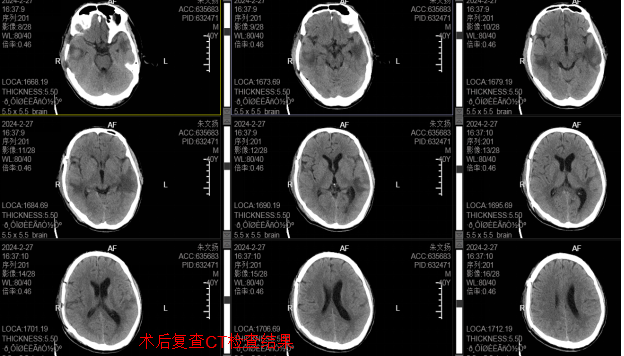

颅脑创伤病人往往是伤情重、情况急、变化快,颅内血肿是颅脑创伤中最常见、最严重的继发性病变,严重的颅内血肿常可压迫大脑引起脑疝从而危及生命。发生颅脑创伤时应及时送诊、及时评估、及时治疗,严重的颅脑创伤更应就地救治,减少不必要的转送,避免错过最佳时机从而加重病情。

目前佛冈人医已完成创伤中心建设,具备创伤中心救治条件及能力,可以做到创伤患者的快速评估、检伤分类和分级诊疗机制,对创伤患者尤其是严重创伤患者进行“早识别、早诊断、早治疗”,按绿色通道流程,对于需要紧急救治的创伤患者,实施“先救治、后付费”,严格规范创伤救治流程,有效降低严重创伤患者的致残率和致死率。